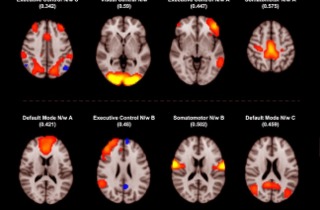

Medical News: Mental health conditions such as anxiety, depression, and bipolar disorder are often discussed in terms of emotions and behavior, but new research shows that the story goes much deeper into the body. Scientists have now uncovered clear biological patterns in the blood that connect these mental disorders to inflammation, metabolism, and even heart-related stress, offering fresh insigh...